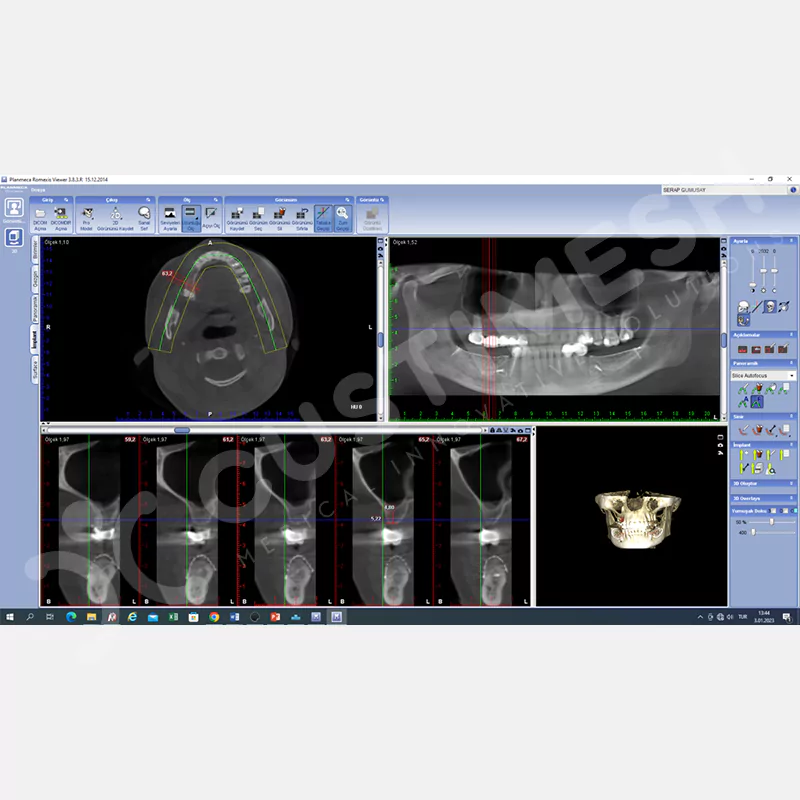

- DICOM

Hastanın DICOM dosyası WeTransfer aracılığıyla custimesh.case@gmail.com adresine gönderilmelidir. *AÇIKLAMA kısmına hekim adı ve Custiplate yapılacak ilgili bölge belirtilmelidir. Custiplate için, Fov genişliği tedavinin uygulanacağı bölgeyi kapsayacak şekilde 0.5 mm kesit kalınlığında Medikal CT çekilmelidir. - HEKİM ONAYI

Custiplate planlanacak bölge dikkate alınarak 3 boyutlu model hazırlanır, hekimin onayına sunulur ve gerekli değerlendirme için hekimle iletişim sağlanır. - ÖDEME